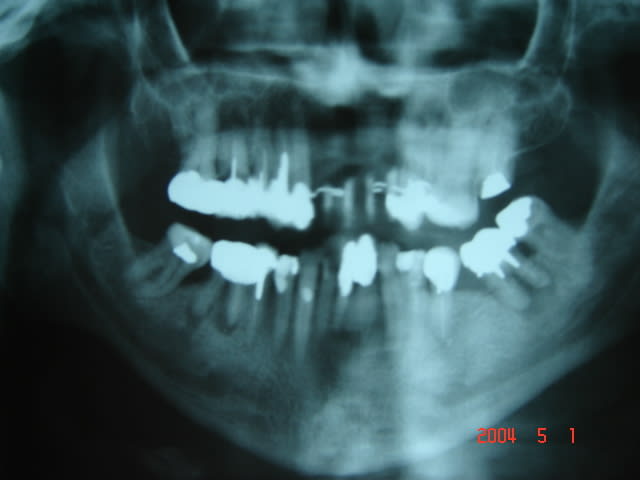

voici la pano ,enfin un peu améliorée..!

Imagerie ghomrani 001 zhbb4t - Eugenol

Imagerie ghomrani 001 seheqa - Eugenol